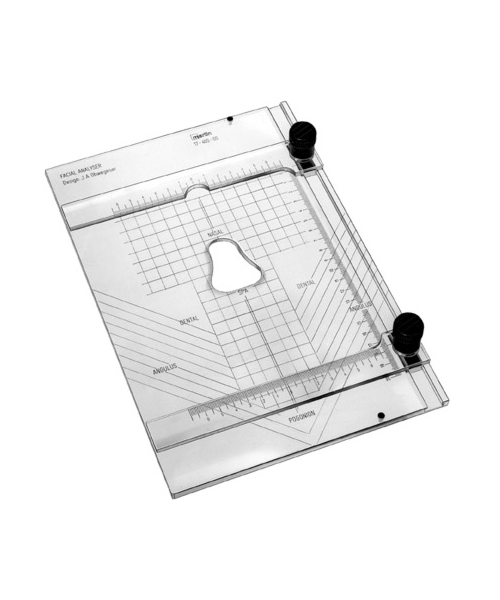

- Diagnostics, Surgical Instruments

Flexometer

- Size : 11 CM - 4 1/4"